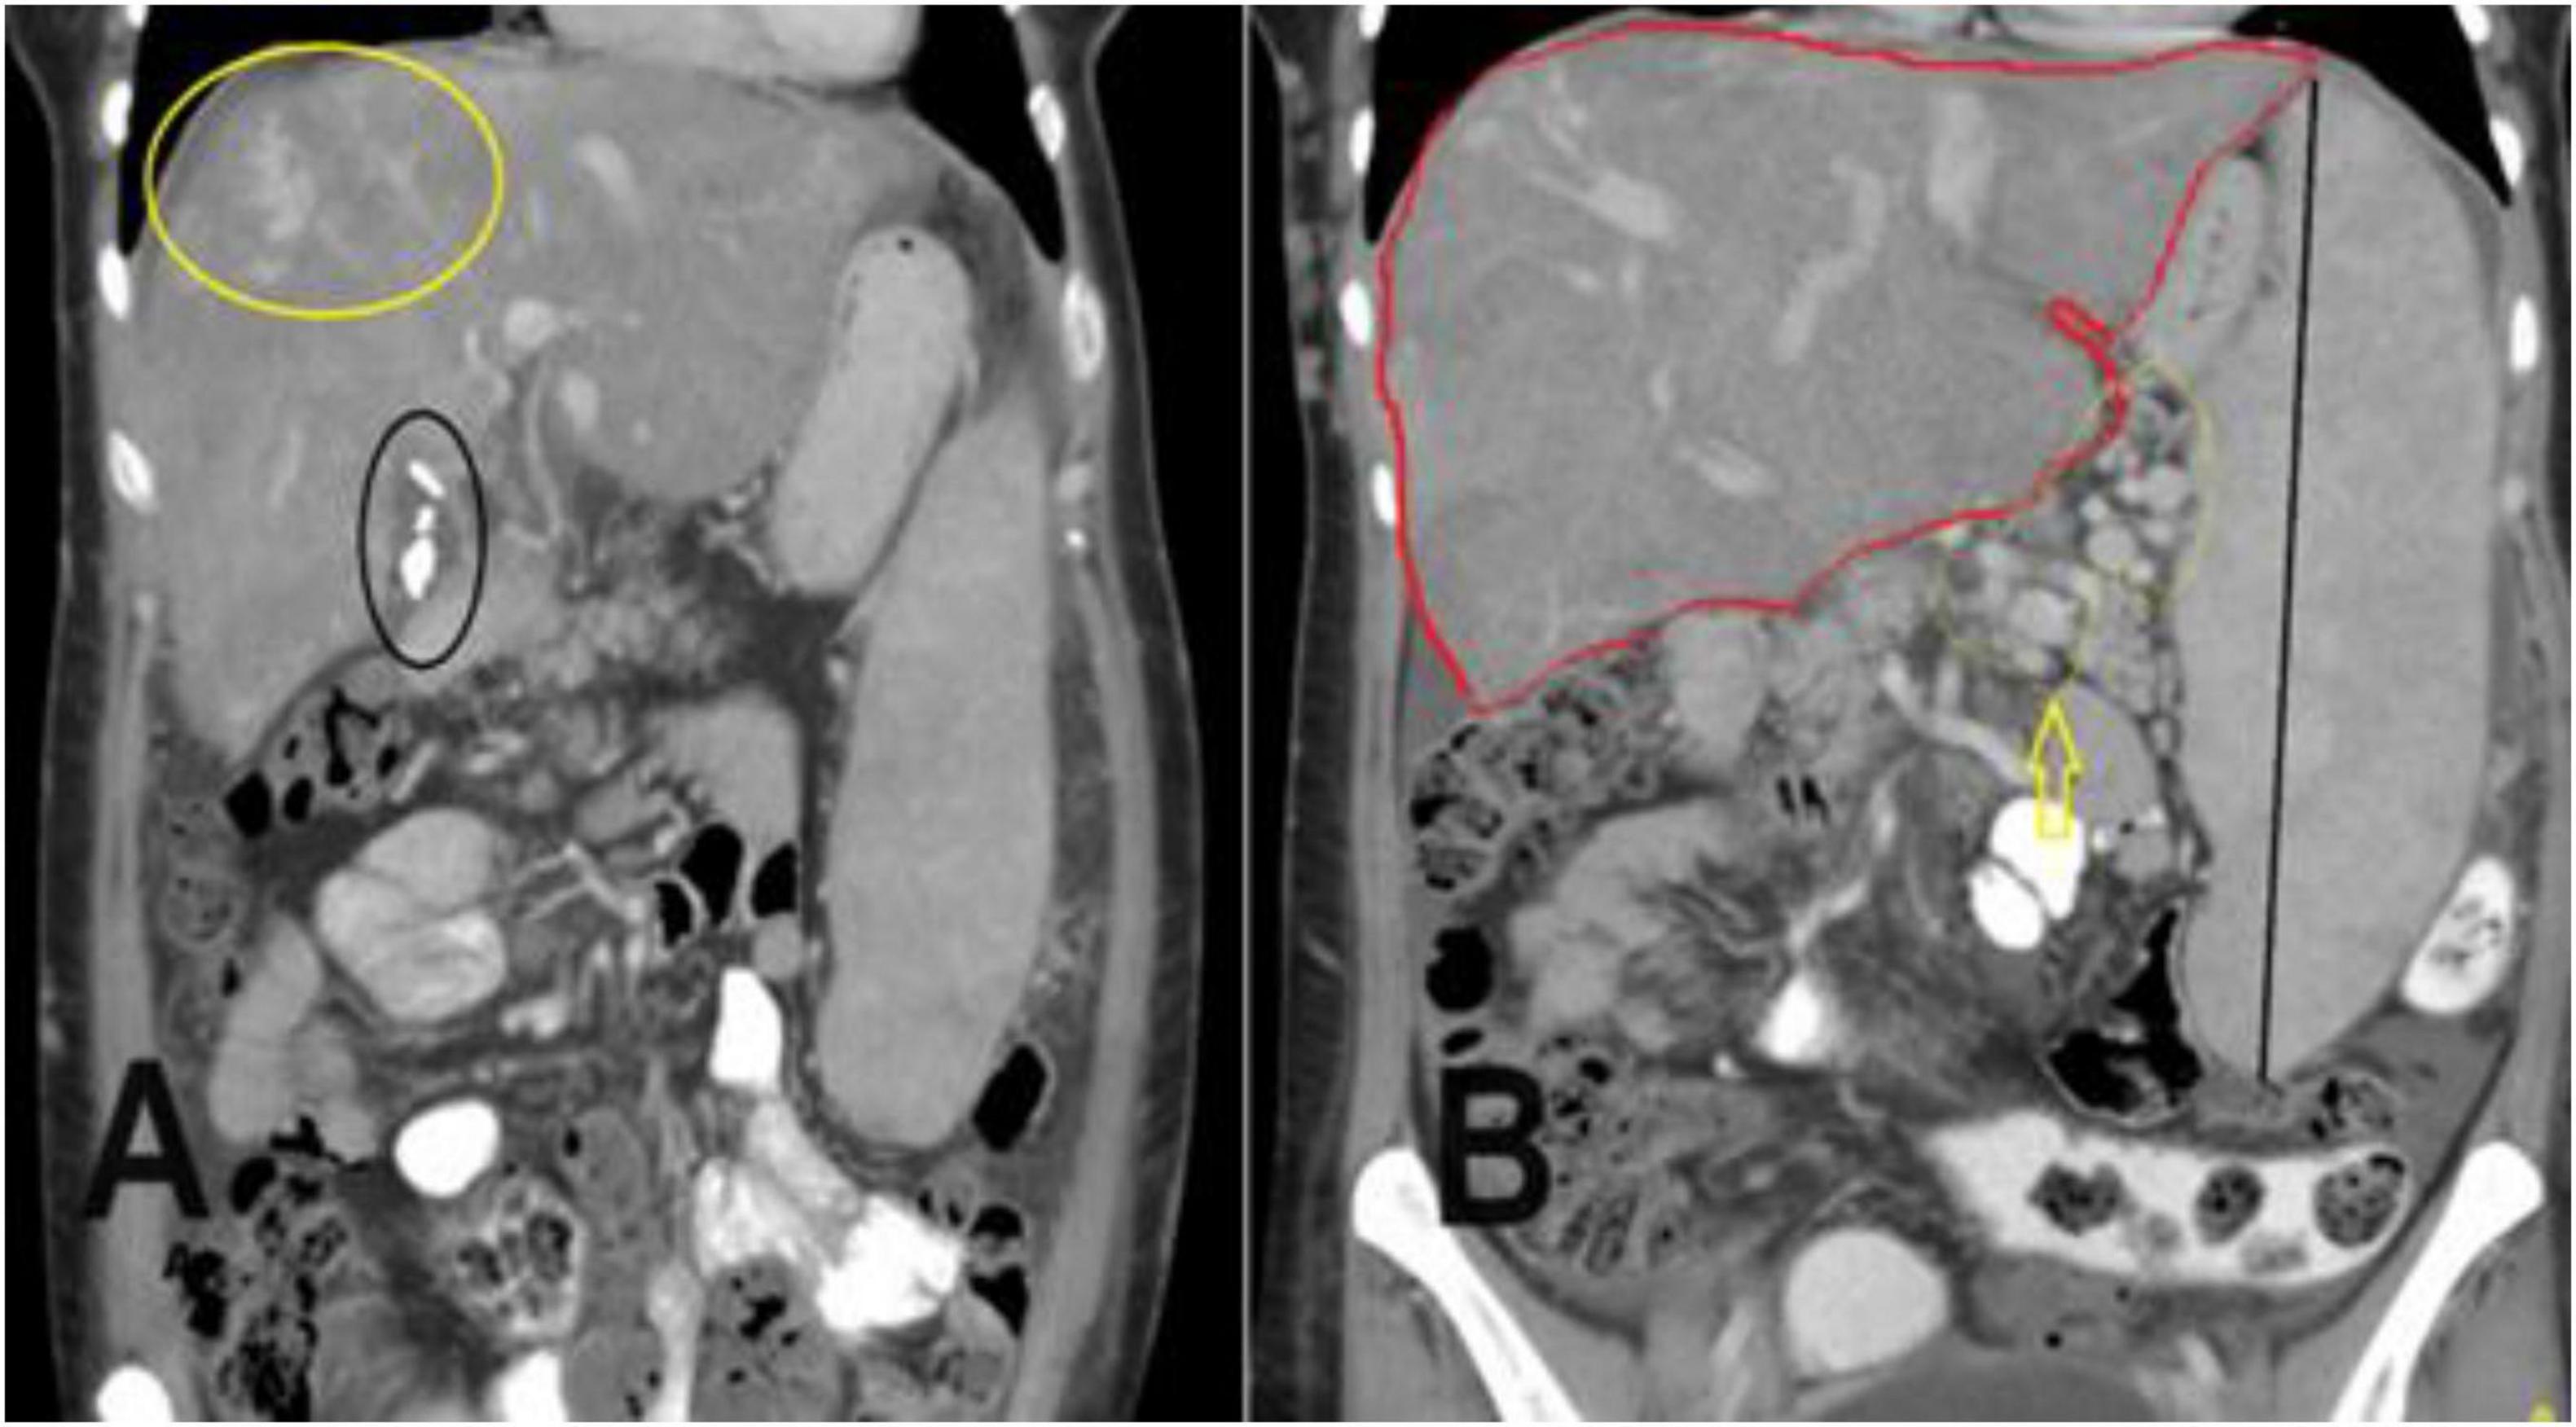

Figure 2. A coronal section of the portal venous phase of the computed tomography (CT) abdomen for the previously mentioned patient as in Figure 1 demonstrates (A) incidental finding of cholecystectomy clips and fluid in the gallbladder fossa indicating recent cholecystectomy. (B) Hepatomegaly and a huge spleen are consequences of Budd-Chiari syndrome (BCS), splenic varices (yellow arrow), and multiple collateral veins in the abdominal wall.

Digital Subtraction Angiography (DSA) is considered a “gold standard” modality to diagnose BCS, but its invasive procedure involving the use of contrast materials and ionizing radiation (42), Doppler US is considered the first modality of choice for initial investigation when BCS is suspected (43), but it highly depends on the operator’s experiences; ultrasound is also affected by excessive ascites and bowel gases (42, 44). CT is widely used in BCS diagnosis, it’s used to evaluate liver parenchyma, HVs, IVC, and venous collaterals (45). However, CT is considered less accurate in the detection of venous abnormalities compared with CDUS and MRI (12). Also, the use of contrast agents may lead to allergic reactions, and possibilities of contrast-induced nephrotoxicity were the major drawbacks (46). MRA is an alternative technology used for vascular assessment in BCS without the use of contrast materials (47). It is also used for the classification of BCS patients (48). A high rate of heartbeats, massive ascites, and uneven breathing were factors of misdiagnosis in MRA of BCS patients (42). The sensitivities and specificities for Doppler in the diagnosis of BCS were 89% and 68%, 89% and 72% for CT, and 93% and 55% for MRI, respectively, indicating higher MRI sensitivity and higher CT specificity compared to both modalities. MRI yielded an AUC of 90.8% compared with 88.4% for CT and 86.6% for Doppler ultrasound (49). This research was conducted to characterize and identify the common feature of Budd Chiari syndrome in the Sudanese population using CT scan, CT and Doppler US are the available and most used diagnostic modalities in Sudan to identify the BCS features, contrast-enhanced liver CT is readily used for abdominal and liver disease scans more frequently than MRI, due to the limited number of MRIs in Sudan. Figures 1, 2 give a clear picture of BCS features and their related complications. Different age groups were investigated; in which BCS affects both children and adults, a median age of 10.5 (2–16 years) was identified (50) which is commonly associated with abdominal distention in more than 86% of children and upper GI bleeding in more than 36% of patients as common primary indication and findings as detected by Ultrasound and MRI in few patients. BCS is rare in children and accounts for more than 16 percent of pediatric liver illnesses in Asia, but less than 0.1 percent in Western nations (51), our present research indicates that the most common age group for affected children was 02–14 years, same results also indicated by different authors including (50, 52). This study focused on different ages as adults were more frequently included resulting from a random collection of data, a common age group affected in adult patients at the time of diagnosis was 39–52 years, as also seen by Ollivier-Hourmand et al. (53) in France, who stated the mean age was 40 ± 14 years. A total of 45 years mean age as in (54). BCS affects both males and females, but in this study, the most affected gender was male at 57.4%, while females represented 42.6% of the total sample distribution. This result is quite different from a variety of studies reported by different authors, as females were commonly affected rather than male gender, as in (55, 56), Female predominance is reported in the West (67%) (57). But also, slight male predominance was reported in India (58) and Japan (59). Dilawari et al. (58) stated that males are commonly associated with IVC obstruction, while females are commonly associated with Hepatic Viens (HV) obstructions. Manifestation of such clinical signs depends on the degree of hepatic vein involvement and portal vein, as in Figure 1A. This study showed that the most common signs and manifestations of BCS were abdominal pain seen in 57.4% of patients, followed by jaundice associated with edema and/or vomiting in 42% of patients. Less frequent signs were seen as abdominal distention as a result of intra-abdominal bleeding in 1.63% of the study populations. Different authors report that hepatomegaly, ascites, abdominal discomfort, and the existence of dilated superficial abdominal wall veins are the main characteristics of BCS (13, 60). To distinguish between vascular and parenchymal liver disease was commonly diagnosed using contrast-enhanced CT abdomen with varying contrast timing. Computed tomography has recently been shown to be an excellent modality of choice for the characterization, classification, and staging of BCS, especially for chronic stages of disease (13). The liver parenchymal appearance showed various patterns of enhancement, with a heterogenous (nutmeg) liver seen in most of the patients 27.87%. In comparison, an enlarged liver also with heterogeneous contrast enhancement was identified in more than 24% of the CT scan results. Liver cirrhosis is a remarkable characteristic of different chronic liver diseases, especially hematogenous-associated diseases. BCS is a rare cause of liver cirrhosis that can be distinguished from other causes of cirrhotic disease by normal values of liver function and prominent portal hypertension (PH) (61). Cirrhosis caused by BCS seen shows 14.8% of patients with cirrhotic heterogeneous liver, as in Table 1. As we previously mentioned, causes of BCS are most commonly due to vascular causes, HV thrombosis due to hemodynamic disorders, or secondary due to tumor thrombus from RCC or HCC (1, 9, 10). Hepatic vein thrombosis was seen in 11 patients (18.03%), A CT scan of the patient with BCS reveals a wide range of findings including biliary diseases, hepatic lesions either benign or malignant lesions, chronic liver diseases such as viral or non-viral conditions, gallbladder stone associated with wall thickening seen in 6.56% of BCS patients, also the background of the shrunken liver with an irregular outline in 4.92%, liver cyst or gallbladder cancer, IVC thrombosis associated with hemangioma, chronic hematological disease, hepatic vein obstruction with tumoral thrombus in IVC, chronic liver disease associated with multiple nodules, and chronic hepatic vein thrombosis as presented in Table 2. Collectively these (CT findings) related to BCS were seen in more than 52% of study populations compared to more than 87% of patients, as reported by Denninger et al. (9); see Table 2. In 80%–91% of instances, the caudate lobe enlarges as a result of distinct venous outflow (62, 63). A “flip-flop” pattern develops during the portal venous phase, with modest attenuation of the liver’s core region due to washout. A different form of venous changes and appearance in computed tomography were identified in this study. HVs were not identified in more than half of the patients diagnosed with BCS (55.73%), narrowing or barely seen hepatic veins, slit-like (compressed) IVC, portal dilatation, dilated celiac, and SM vein; all these changes were seen in Sudanese populations, as presented in Table 3. BCS is linked to varying degrees of variceal alterations because of venous involvement. Commonly, no variceal changes are seen with BCS in a significant percentage of the patients including more than 59% of them, but due to these obstructive changes and increased vascular permeability. The most common site of varices is the lienorenal and gastro-esophageal region seen in 37.7% of patients with BCS and varying degrees of involvement in gastric and esophageal veins. Still, many cases were not associated with varices in more than 59% of patients, see Table 4. Naganuma et al. (64) reported that; BCS is one of the main causes of intrahepatic and abdominal collaterals. Hepatomegaly and ascites are caused by acute blockage of the hepatic venous outflow (attenuation/thrombosis of HVs and/or IVC). Venous thrombosis causes the portal venous blood influx to be delayed or reversed as well as an increase in sinusoidal pressure. In the acute form, hepatic necrosis happens quickly, and venous collaterals have not yet formed (13, 63). This study reported that more than 73.7% of patients presented with ascites (associated with an umbilical hernia in 1.63%) of the patients. In addition to other rare complications such as compressed duodenum, splenic, and SM vein occlusion, as shown in Table 1. Ascites is commonly associated with older ages, especially 39–52 years as the peak age of patients is strongly linked to such complications. Radiologic investigations of BCS are non-invasive procedures. US allows the assessment of hepatic venous flow and heterogeneity, while CT and MRI can depict HVs thrombosis and IVC occlusion or compression.